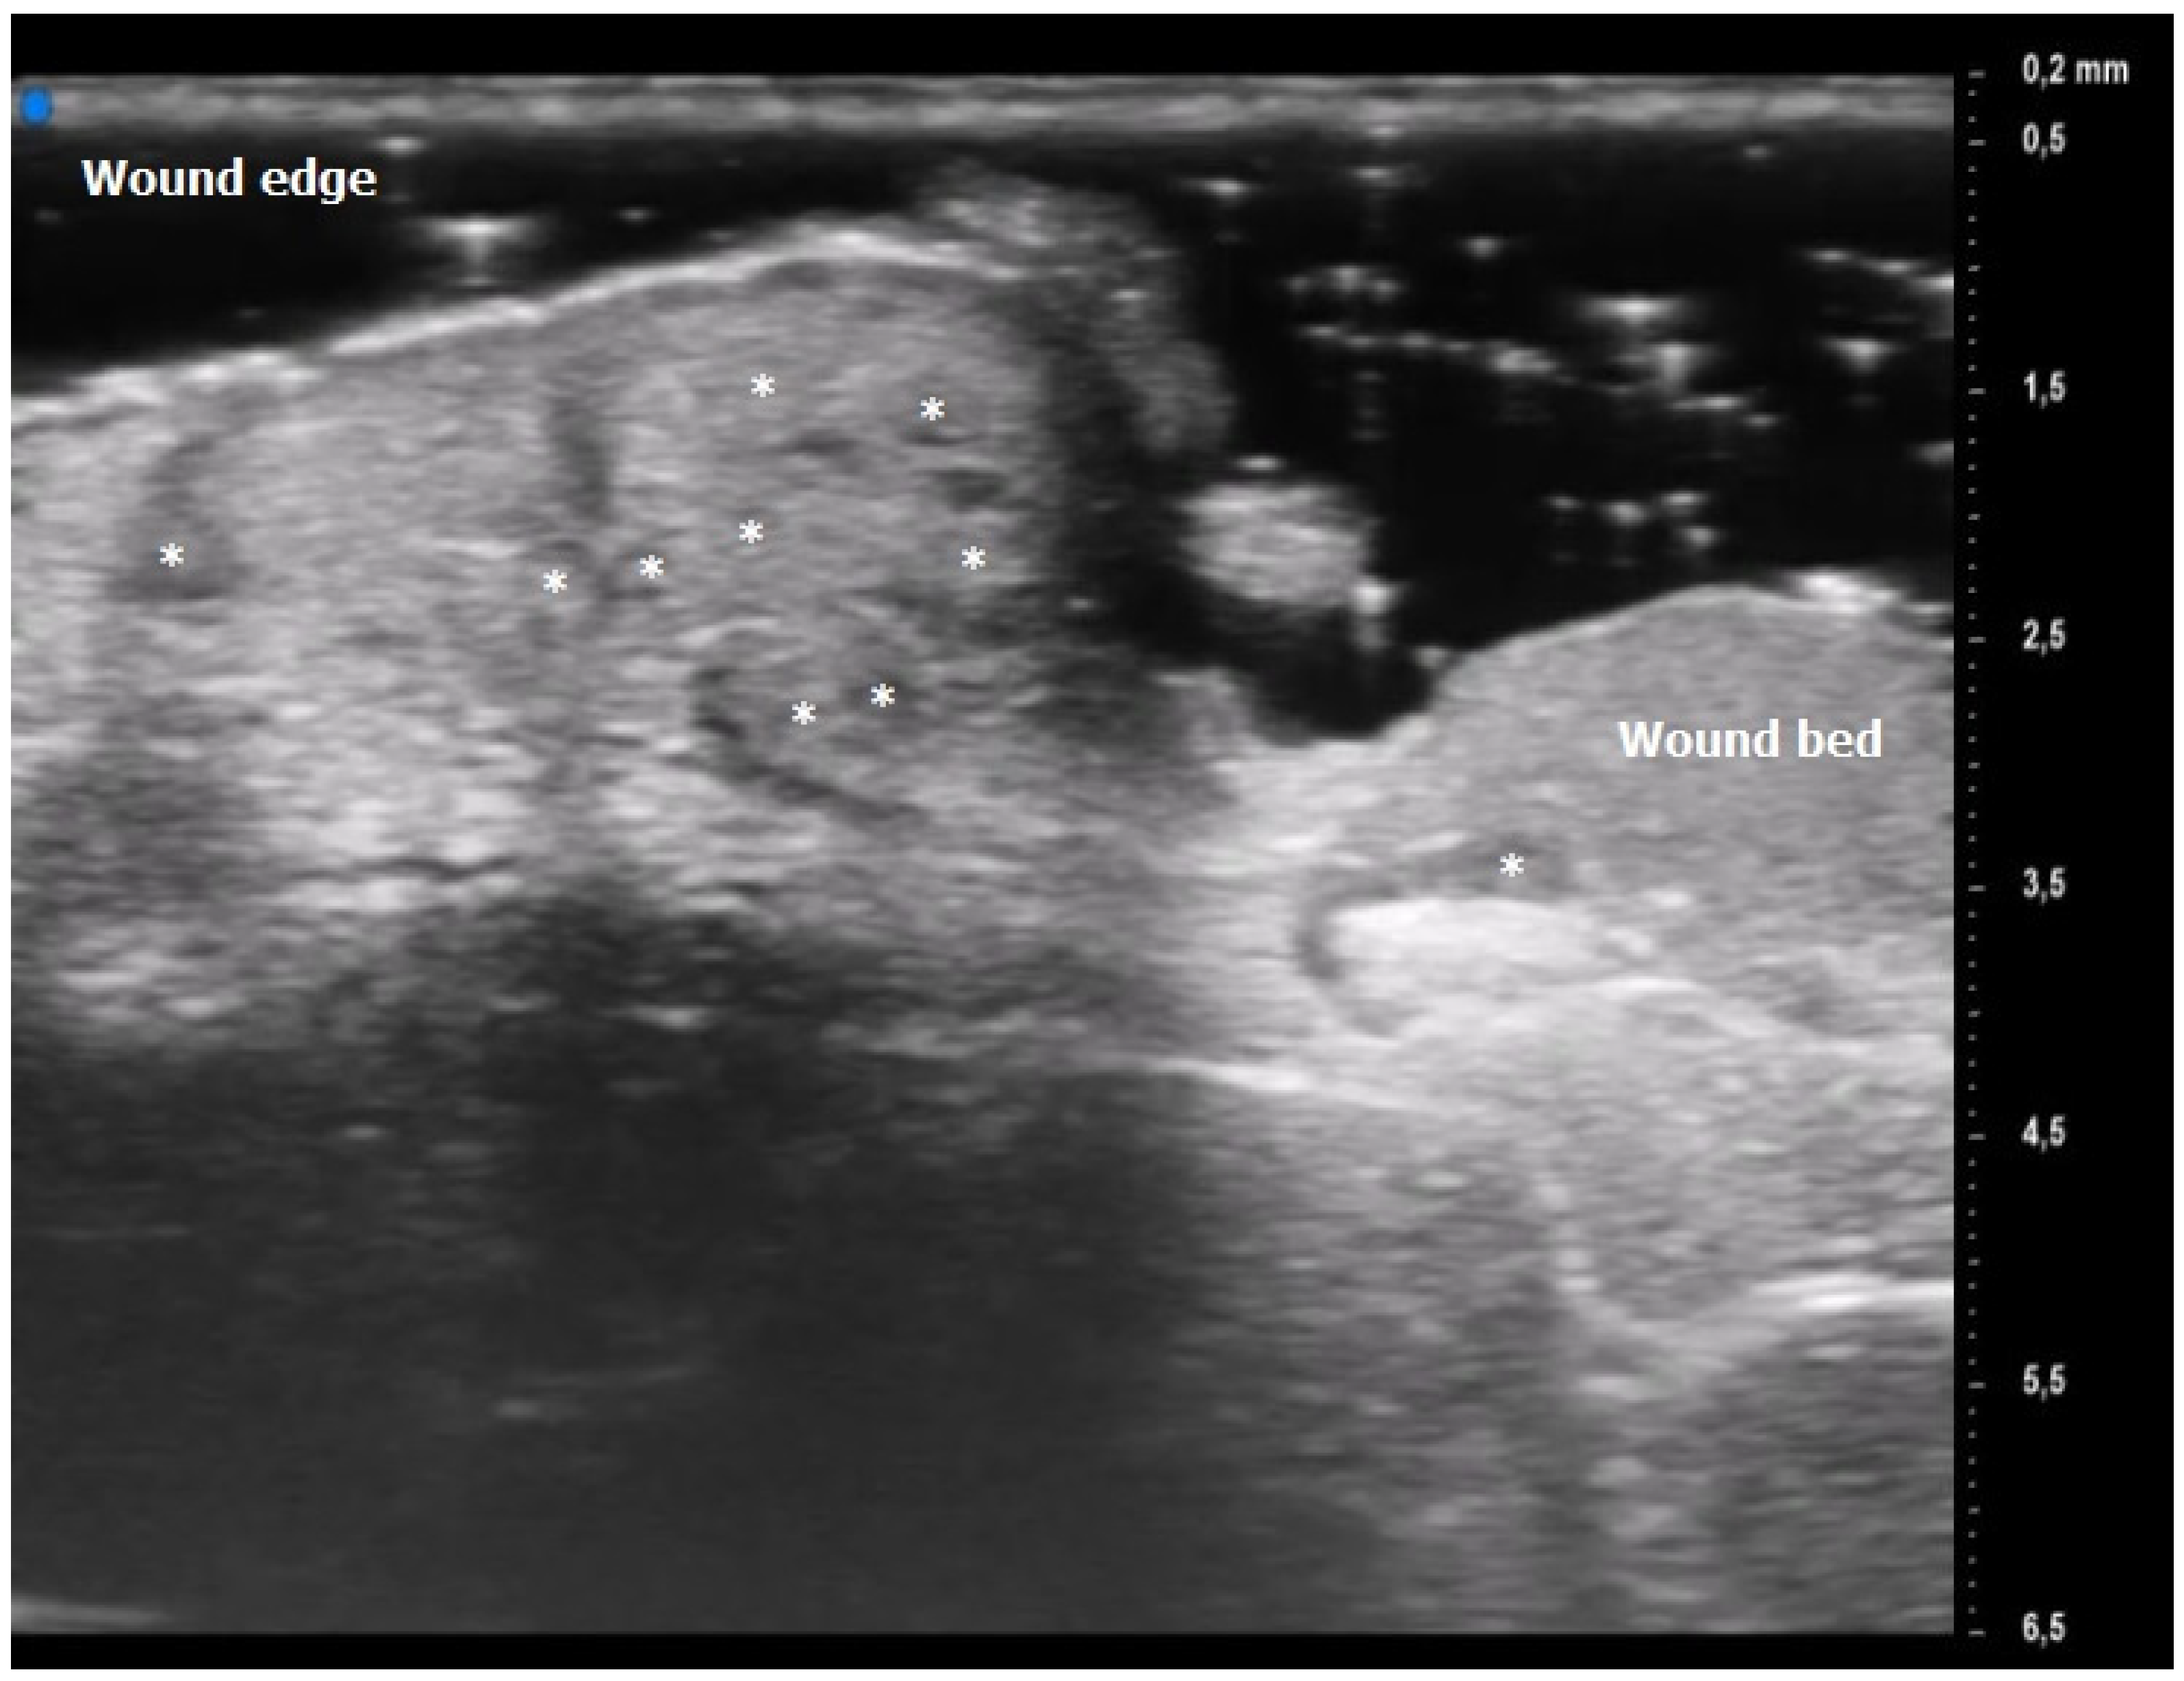

Figure 2.

Pyoderma Gangrenosum (PG) Ultra-High Frequency UltraSound (UHFUS) features during the inflammatory phase (T0): oval hyperechoic structures (*) surrounded by hypoechoic borders predominantly located at the ulcer edge.